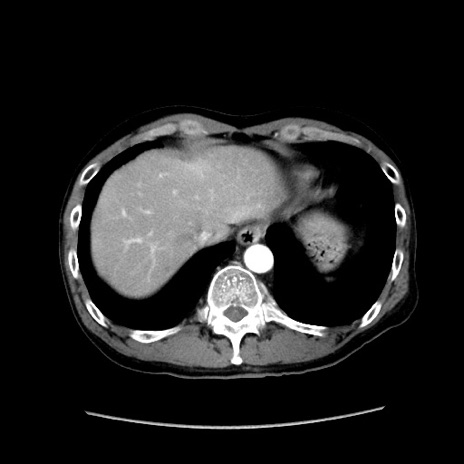

冠状断像

【症例】40歳代 男性

【主訴】腹痛

【現病歴】4時間ほど前に電車に乗車中に臍部上より腹痛出現。徐々に増悪し起立困難となり、救急外来受診。生ものは数日食べていない。今朝お雑煮を食べた。

【身体所見】BT 36.8℃、BP 117/84mmHg、HR 91/min、SpO2 97%、苦悶様、腹部:臍上部広範囲圧痛あり、反跳痛±

【データ】WBC 8100、CRP 0.03